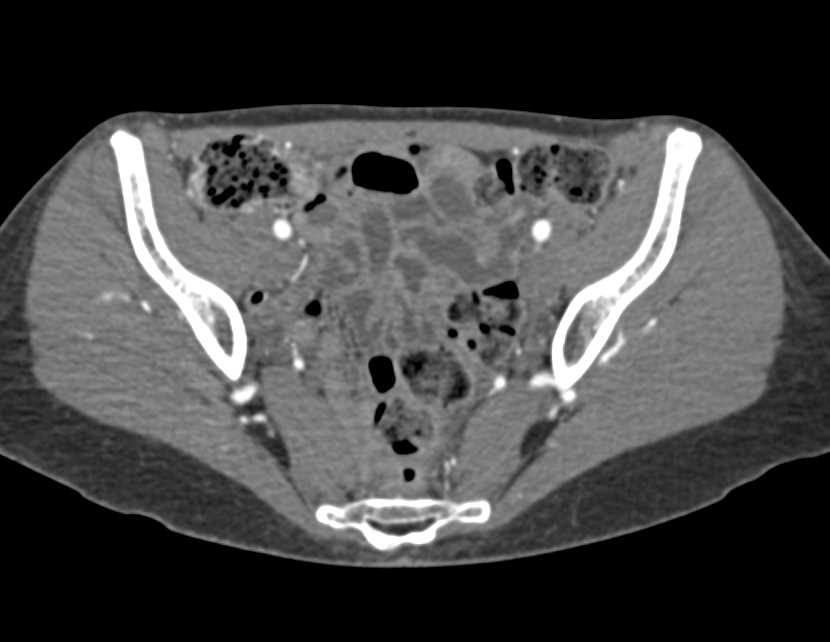

Multiple Arteriovenous Malformations (AVMs) in the Liver in Patient with Hereditary Hemorrhagic Telangiectasia (HHT) Disease